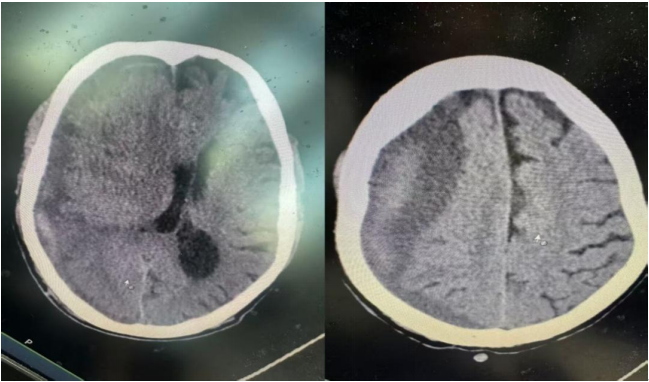

患者周某因颅脑外伤后左侧肢体瘫痪7天入院,入院时左侧肢体肌力1级、右侧肌力5级,颅内高压持续加重将危及生命。颅脑CT提示,其右侧亚急性硬膜下血肿约131毫升,脑组织中线偏移10毫米,病情危重。